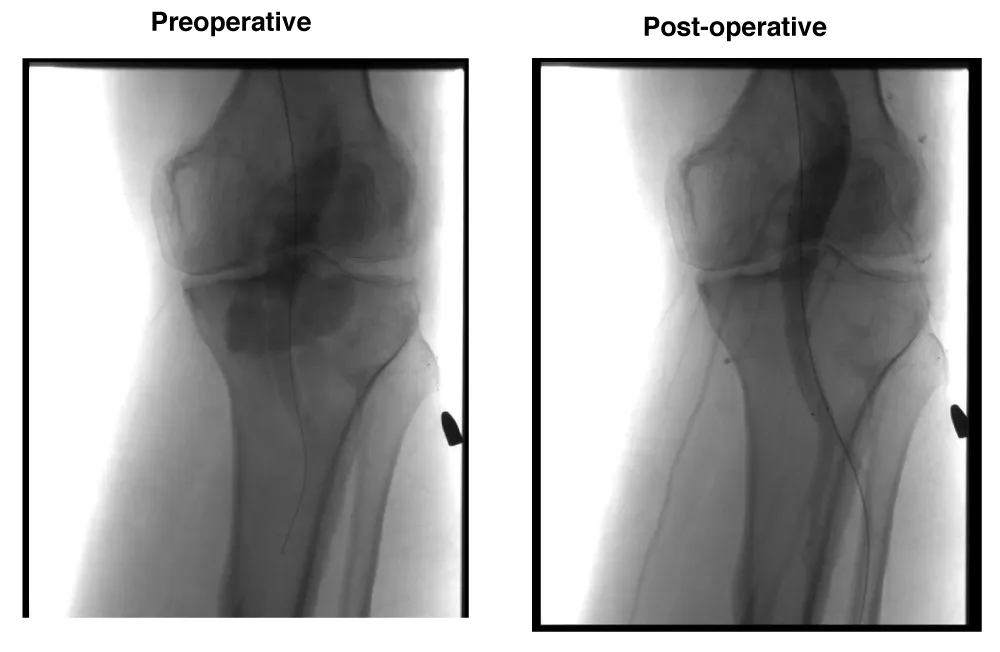

A male patient, 74 years old, with arterial hypertension and diabetes was admitted with right Lower limb rest pain due to acute arterial occlusion. The patient underwent AngioCT scan which demonstrated a 26 mm popliteal artery aneurysm thrombosis. The patient was submitted to endovascular surgery with popliteal implant of endoprosthesis Wrapsody® 12x80 mm at distal neck and Wrapsody 12x80 mm at proximal neck, followed by catheter balloon dilatation, after proper intra-arterial thrombolysis (Figure 3). The patient was discharged from the hospital on the first day post-operative with Rivaroxaban 20mg/day and a 2-month follow-up showed endoprosthesis patency with complete resolution of the previous symptoms.

Figure 3: Endovascular thrombolysis and stenting of a 74-year-old male with acute thrombosed 26 mm popliteal artery aneurysm: Preoperative CT angiography reveals occlusion and aneurysmal dilation. Postoperative image confirms successful thrombolysis and exclusion with two Wrapsody® stents (12×80 mm each), with reestablished distal perfusion.